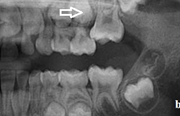

Ravijärgne seis. Jäävhammas on täielikult lõikunud.

) Röntgenülesvõte. Ülemise esimese jäävmolaari lõikumine on takistatud 2. piimamolaari tõttu

Esimese jäävmolaari ektoopiline lõikumine